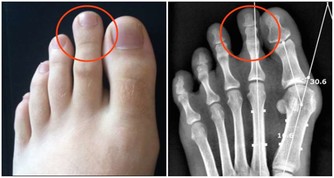

***3.促進鈣鐵的吸收***

食物中的鐵分為血紅素鐵和非血紅素鐵,血紅素鐵是二價鐵,吸收率較高。非血紅素鐵是三價鐵,須在體內轉化成二價鐵才可被人體吸收。而維生素C可將三價鐵還原成二價鐵,促進鐵的吸收。多吃富含維生素C的食物可促進身體對鐵的吸收,是一種預防缺鐵性貧血比較好的方法。

鈣在消化道呈可溶狀態是被吸收的基本條件,維生素C在胃中可形成一種酸性介質,防止不溶性鈣絡合物的生成及發生沉澱,促進鈣的吸收和利用。